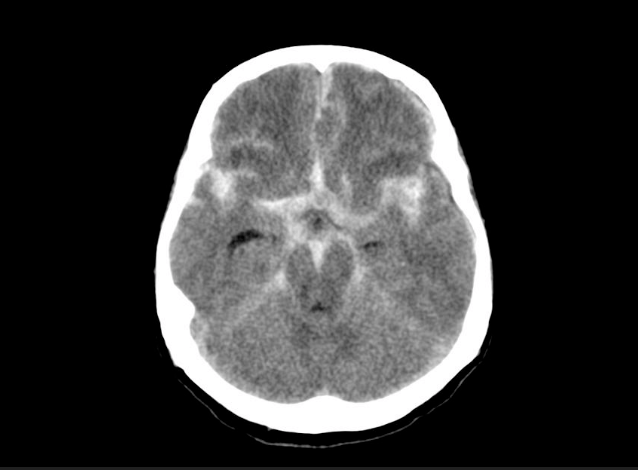

This is the finding on this CT.

What is subarachnoid hemorrhage?